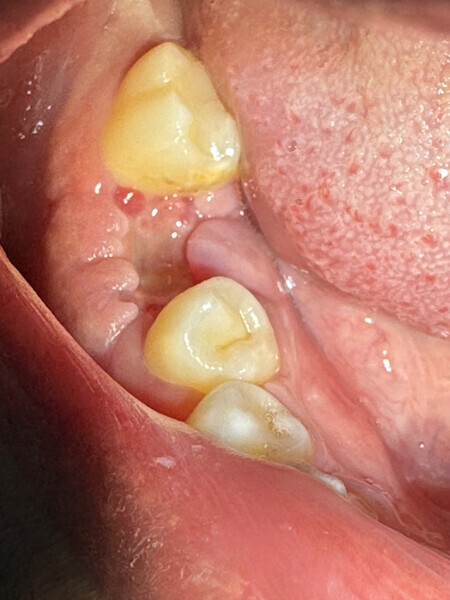

On pourra remarquer que la membrane a été volontairement laissée exposée, afin de ne pas lever de lambeau vestibulaire ou lingual. Grâce à ceci, nous avons pu conserver la totalité de cette muqueuse attachée, ce qui nous permettra d’obtenir un résultat esthétique bien meilleur lors de la reconstruction prothétique, qu’elle soit traditionnelle (bridge ou prothèse amovible) ou sur implants, en permettant d’avoir un profil d’émergence le plus proche possible du naturel (Figs. 4–8).

Dans notre cas, la pose d’implant a été privilégiée sur ce patient, jeune, avec des dents saines de part et d’autre de l’avulsion.